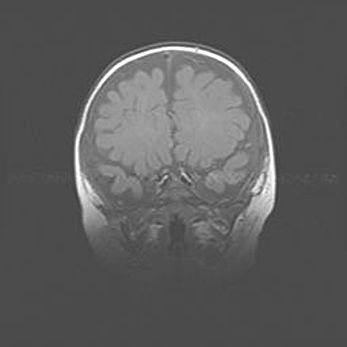

Аномалия Денди-Уокера. Признаки гипоплазии мозолистого тела.

Возраст: 5 месяцев 3 дня

Вес: 5550 г

Пол: мужской

Окружность головы: 39 см

Срок гестации: 40 недель

Аномалия Денди-Уокера – это порок развития головного мозга, для которого характерна триада симптомов: гипотрофия или аплазия червя мозжечка и/или полушарий мозжечка, расширение четвёртого желудочка с формированием ликворной кисты задней черепной ямки, гипертензионная гидроцефалия различной степени.

Гипоплазия мозолистого тела относится к дефектам внутриутробного этапа развития мозговой ткани, возникающим в процессе закладки структур головного мозга, что происходит на начальных этапах развития эмбриона.